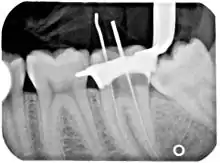

في الحالة التي يشكل فيها السِّن تهديدا (بسبب النَخَر، التشقق، الخ) والتي تعتبر فيها العَدْوَى المستقبلية أكثر احتمالاً أو لا مفر منها، يُنصح باسْتِئْصالُ اللُّبّ، إزالة الأنسجة اللُّبِّيَّة، لمنع حدوث العَدْوَى. عادة، تكون بعض الالتهابات وأو العَدْوَى قد وجدت داخل أو تحت السِّن. لعلاج العَدْوَى وحفظ السِّن، طبيب الأسنان يحفر إلى الغُرْفَةُ اللُّبِّيَّة ويزيل اللُّبّ المصاب ومن ثم يُخرج العصب من نَفَقُ الجَذْرِ (أنفاق الجذور) بواسطة أداة يَدَوِيّة على شكل إبرة طويلة تعرف بمِبْرَد الأسنان (مِبْرَد الأسنان,H مِبْرَد الأسنانK ). نبدأبمِبْرَد سِّن صغير (يطلق عليه أحياناً 'مِسْبارُ قَناةِ الجَذر') ويتم استخدام مِبْرَدأكبر تدريجيا لتوسيع الأنفاق الجذرية. تستخدم هذه العملية لإزالة الحطام والأنسجة المنعدية وتسهل اختراق أكبر لمحلول الإِرْواء. بعد ذلك، طبيب الأسنان يَملأ كل من أنفاق وغرف الجذور بمادة خاملة ويختم على الجزءالمفتوح. هذا الإجراء يعرف بمُعالَجَةُ قَناةِ الجَذْر. مع إزالة الأعصاب وإمدادات الدَّممن الأسنان، من الأفضل أن تكون الأسنان مزودة بالتاج.

مادة التعبئة المعيارية هي الطبرخي، عبارة عن بلمر طبيعي يُحضر من اللاتكس من شجرة البيرشا (الأسم العلمي طبرخي ). وتنطوي هذه التقنية اللبية المعيارية على إدراج مخروط الطَبْرَخِيّ ("أَقْماعٌ طَبْرَخِيّة") في القناة الجذرية النظيفه جنبا إلى جنب مع مِلاَطُ الخَتْم.[5] طريقة آخرى تستخدم الطَبْرَخِيّ المذاب بواسطة الحرارة الذي يتم بعد ذلك حقنه أو ضغطه في ممر نَفَقُ الجَذْرِ (أنفاق الجذور). لكن، الطَبْرَخِيّ ينكمش بينما يبرد، مما يجعل الطريقة الحرارية غير موثوقة، وأحيانا يتم استخدام مجموعة من التقنيات. الطَبْرَخِيّ ظليل للأشعة، مما يتيح التحقق بعد ذلك أن ممرات نَفَقُ الجَذْرِ قد تم تعبئتها كاملة، بدون فراغات. تم اخترع مادة حشو بديلة في بدايات 1950 بواسطة انجيلو سارجنتي. خضعت لعدة صيغ على مر السنين (N2، N2 العالمي، RC-2B، RC-2B الأبيض)، ولكن كلهم يحتوون على بارافورمالدهيد. بارافورمالدهيد، عند وضعها في نَفَقُ الجَذْرِ، تشكل الفورمالديهايد، التي تخترق وتعقم المرور. ثم يتم تحويل الفورمالديهايد نظريا إلى مياه غير ضارة وثاني أكسيد الكربون. والنتيجة كانت أفضل من نَفَقُ الجَذْرِ المعمول بالطَبْرَخِيّ وفقا لبعض التحقيقات. بيد أن هناك نقصا غير قابل للجدل في الدراسات العلمية وفقا للمجلس السويدي على تقييم التكنولوجيا الصحية. [بحاجة لمصدر] في حالات نادرة، المعجون مثل أي مادة أخرى يمكن إجبارها لتمر منذِرْوَةُ الجَذْر إلى العظام المحيطة. إذا حدث ذلك، سوف يتم مباشرة تحويل الفورمالديهايد إلى مادة غير ضارة. الدَّم طبيعياً يحتوي على 2 ملغ من الفورمالديهايد في كل لتر من الدَّم والجسم ينظم هذا في ثوان. المتبقي من فرط التعبئة سيتم امتصاصه تدريجيا والنتيجة النهائية هي جيدة بشكل طبيعي. في عام 1991 قرر مجلس ADA على أن مداواة الأسنان بهذه الطريقة "غير مستحسنة"، ولم يتم تدريسها في أي كلية طب الأسنان الأمريكية. والأدلة العلمية في المعالجة اللُّبِّيَّة كانت ولا تزال ناقصة.[6] تقنية سارجنتي لها دعاة، الذين يعتقدون أن N2 أقل تكلفة وإيضاً على الأقل آمن مثل الطَبْرَخِيّ.[7]